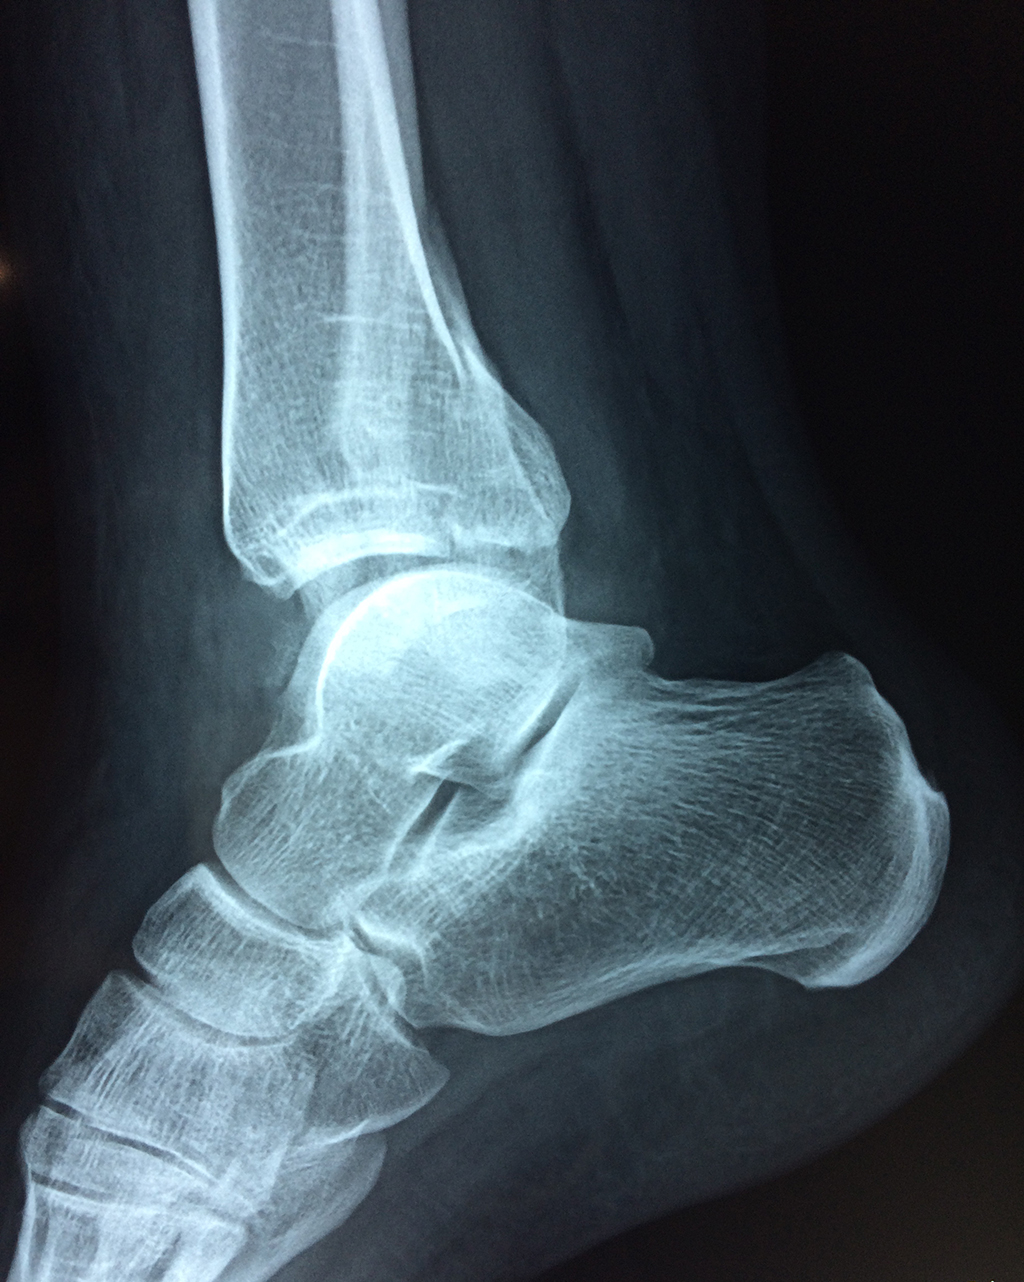

Una fractura de tobillo es la rotura de uno o más de los huesos del tobillo. Estas fracturas pueden ser:

- La fractura se extiende hasta la articulación del tobillo (fractura intra-articular).

Cuando se necesita cirugía, es probable que esta implique el uso de clavijas de metal, tornillos o placas para sostener los huesos en su lugar mientras la fractura se consolida. Los elementos de soporte pueden ser temporales o permanentes.